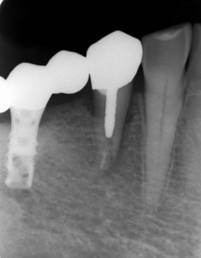

歯周病で抜歯せざるを得ず、インプラントを希望されたケース(使用インプラントはスプライン)

術前。すべての歯が歯周病の末期状態でブリッジ全体がうごいて噛めないとの訴え。右上の犬歯が腫れていました

固定式のブリッジが入っていましたが歯周病で動いています

術前パノラマレントゲン写真。根の周りが黒くなり、骨がなくなっていることがわかります